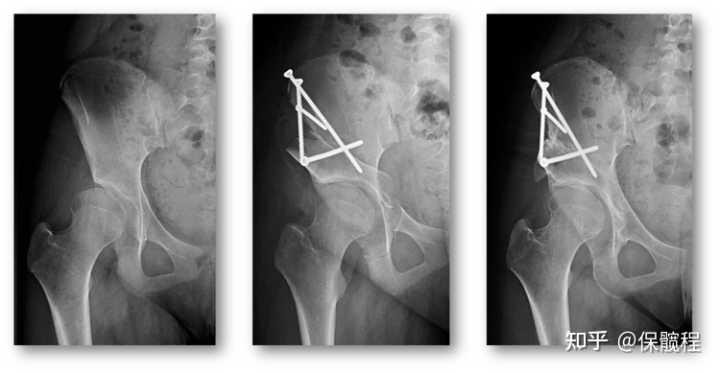

对于髋臼和股骨头形状一致的髋关节,我们只需要做改变髋臼方向的手术,而不需要改变髋臼的形状。如果畸形不重,我们一般选择Salter截骨术;如果畸形较重,Salter截骨术不能够达到理想的矫形,我们会选择创伤较大,但矫形能力更强的三联截骨术。

治疗这一年龄段的髋关节发育不良,以改善髋关节覆盖、增加髋关节稳定性为主要目的,髋臼周围截骨术(也称PAO, Ganz截骨)被大多数业内医生认为是最佳选择,其具有显著优势:能够各个方向矫正髋臼,便于畸形纠正;保持骨盆后柱完整,患者术后可早期下地康复;保留髋臼血运,无髋臼骨坏死的发生;截骨不进髋臼,不增加关节磨损;不改变骨盆整体形态,不影响妊娠及内脏功能;只用螺钉固定,经济压力小……髋关节覆盖明显不足,或虽然影像上看只是临界发育不良但症状明显,且保守治疗不能有效缓解症状的患者,都可以考虑进行手术矫正。